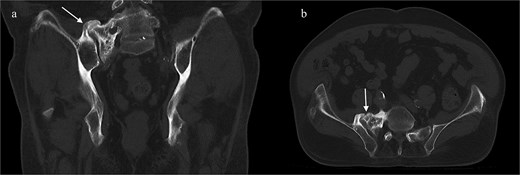

A CT of the pelvis showed significant hyperostosis along the anterior right SI joint and a pseudoarthrosis between the L5 transverse process and the sacral ala that was osteoblastic-appearing in nature (Fig. 1). A SPECT-CT demonstrated increased uptake along the same area, suggestive of inflammatory degenerative changes (Fig. 2).

Coronal CT pelvis (left) and axial (right) demonstrated hyperostosis along the right SI joint suggestive of an osteoblastic lesion between the L5 transverse process and sacral ala (arrows).